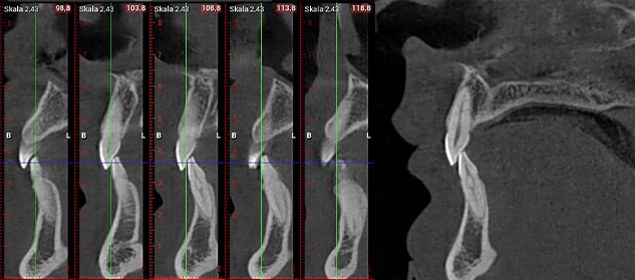

>   Obraz z badania CBCT – szczegóły zębów i wynik analizy / Obraz z badania CBCT – szczegóły zębów i wynik analizy.